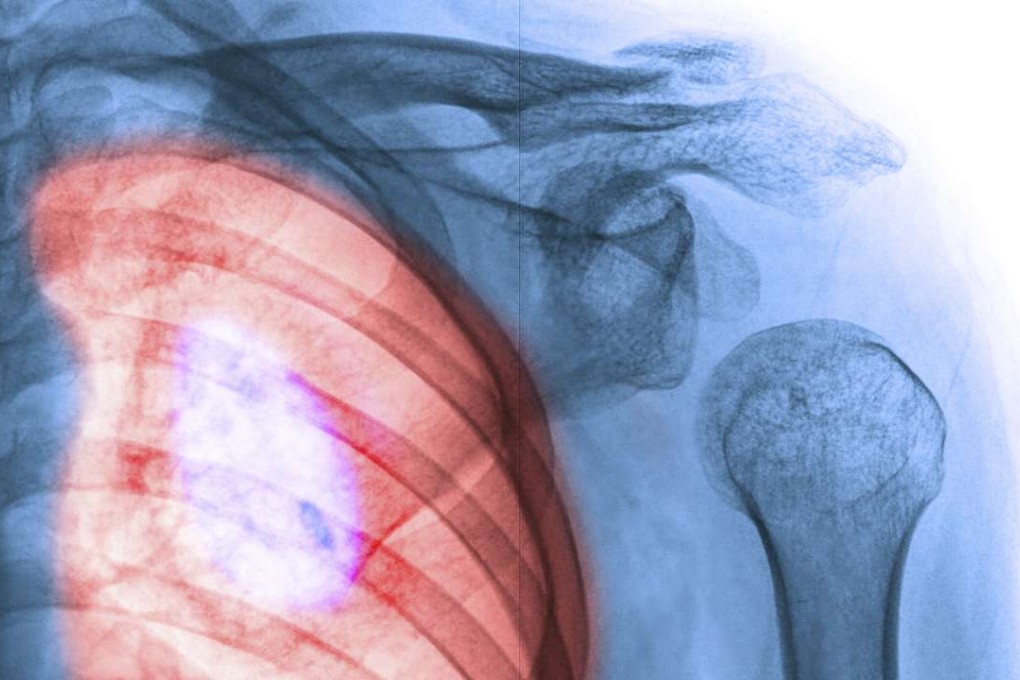

A study has revealed new genes linked to chronic lung disease.

The world’s biggest probe of the genetics of lung health yielded 43 new gene variants linked to chronic obstructive pulmonary disease (COPD), a major cause of death. COPD is a bundle of incurable lung ailments, including emphysema and chronic bronchitis. People with the wrong genetic makeup who also smoke are especially at risk, a team of scientists writes in the journal Nature Genetics.